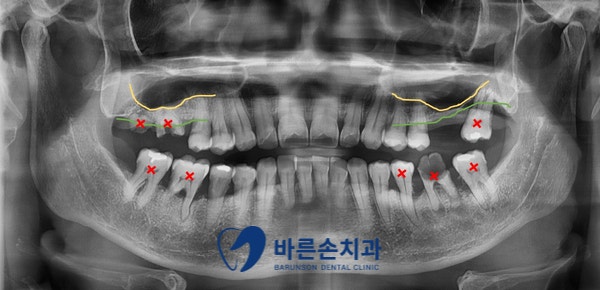

파노라마 엑스레이 촬영 후, 치료 계획을 세웁니다.

X 표 치아들은 발치하고, 임플란트를 하기로 계획합니다.

상악동 함기화(노란선)로 인해, 상악동 공간에 뼈가 많이 부족하고,

치은연하(잇몸 밑으로 내려간) 치석으로 인해 치주염이 심합니다.